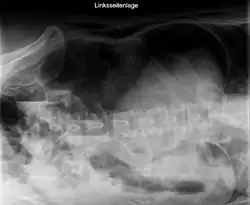

Die Diagnostik basiert auf der körperlichen Untersuchung und der Ultraschalldiagnostik. Bei Verdacht auf eine Darmperforation kann oftmals freie Luft in der Röntgenübersicht oder in der Computertomographie (deutlich sensitiver) nachgewiesen werden. Die Computertomographie kann darüber hinaus häufig die Ursache (z. B. Divertikulitis, Tumor des Dickdarms) identifizieren oder Komplikationen (z. B. Abszess, Fistel) aufdecken.